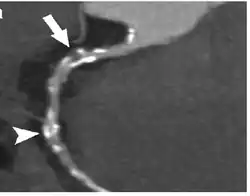

Coronary CT calcium scan

A coronary CT calcium scan is a computed tomography (CT) scan of the heart for the assessment of severity of coronary artery disease. Specifically, it looks for calcium deposits in the coronary arteries that can narrow arteries and increase the risk of heart attack.[17] This severity can be presented as Agatston score or Coronary Artery Calcium (CAC) score. The CAC score is an independent marker of risk for cardiac events, cardiac mortality, and all-cause mortality.[18] In addition, it provides additional prognostic information to other cardiovascular risk markers.[18] A typical coronary CT calcium scan is done without the use of radiocontrast dye, but it can possibly be done from contrast-enhanced images as well, such as in coronary CT angiography.[19]